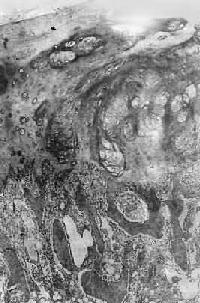

图17-3 骨软骨瘤 图示特征性的三层结构,即最表浅的纤维层,中间的软骨层(软骨帽)和深部的松质骨 【临床病理联系】 骨软骨瘤一般无明显症状,只是局部肿块形成。有时肿块压迫周围组织,引起疼痛和不适。如果肿块体积迅速增大,软骨帽增厚至1cm以上,则须考虑恶变的可能,这在多发性者比单发性者多见。本瘤如手术切除不彻底,则易复发,多发生在1年或数年后。 (二)软骨肉瘤 软骨肉瘤(chondrosarcoma)是从软骨细胞发生的原发性恶性骨肿瘤,由肿瘤性软骨细胞及软骨基质组成。软骨肉瘤是颇为常见的恶性骨肿瘤,其发病率仅次于骨肉瘤,其发病年龄多在中年以后,多见于40~70岁,根据发病部位不同,可分为中央型及周围型两种。中央型从骨髓腔发生,肿瘤为骨皮质所包绕或穿破骨皮质,多见于长管状骨,特别是股骨和胫骨;周围型从骨肿瘤表层出发,向周围软组织及骨皮质侵犯,多见于骨盆、肩胛骨及肋骨等。少数软骨肉瘤来自软骨瘤和骨软骨瘤之恶变。 【病理变化】 肉眼观,中央型软骨肉瘤主要发生在骨髓腔内,呈灰白色、半透明的分叶状肿物,其中常见淡黄色的钙化或骨化小灶。这些钙化或骨化小灶在X线片上可以看到,对诊断软骨肉瘤很有帮助,但高度恶性的软骨肉瘤钙化常不明显。随肿瘤的增大可使骨髓腔变大并侵犯骨皮质,骨外膜受刺激后,可有反应性新骨形成,使受累骨皮质增厚。恶性程度较高的软骨肉瘤,在早期即可穿破骨皮质,向软组织内扩展,形成较大的肿块,周围没有新骨形成。外围型软骨肉瘤瘤体主要在骨外,其表面被覆一层薄而不完整的包膜。以上两型软骨肉瘤均常发生粘液变、出血及囊性变等继发性变化。 镜下观,肿瘤的分化程度差异很大,分化好的软骨肉瘤在镜下易误诊为软骨瘤,但在肿瘤的边缘可以找到瘤细胞的异型性,如核肥大、深染,出现较多的双核、巨核和多核瘤巨细胞,并可见明显核仁(图17-4)。在分化差的软骨肉瘤则上述瘤细胞的异型性很明显,核分裂像也多见。软骨肉瘤的基质可为与一般透明软骨相似的透明基质,也可为粘液样基质,常见于恶性程度高的软骨肉瘤。

图17-4 软骨肉瘤 软骨细胞大小不等,有的较大。许多细胞有肥硕的胞核,有的有双核 【临床病理联系】 局部疼痛及肿块往往是软骨肉瘤的主要症状。近关节的肿瘤常影响关节活动。盆骨的巨大软骨肉瘤可压迫邻近器官,引起相应症状。软骨肉瘤的分化程度对临床经过有一定影响,分化较好的软骨肉瘤往往生长较慢,预后较好。软骨肉瘤一般比骨肉瘤生长慢,转移也较晚。血道转移可至肺、肝、肾及脑等处,淋巴结转移极罕见。软骨肉瘤术后常易复发,多次复发常使恶性程度增加。 (三)骨巨细胞瘤 骨巨细胞瘤(giant cell tumor of bone)是一种具有局部侵袭性及复发倾向的原发性骨肿瘤。由梭形和卵圆形的基质细胞(stromal cell)及大量散布在其间的多核巨细胞组成,肿瘤间质富于血管。由于本瘤内有大量多核巨细胞,因而称为巨细胞瘤;又因过去认为这些多核巨细胞是破骨细胞,故也称为破骨细胞瘤(osteoclastoma)。本瘤的组织来源未明,以上各名称纯系形态学的描述性命名。在我国骨巨细胞瘤的发病率较高,仅次于骨软骨瘤和骨肉瘤,居第三位。本瘤好发年龄为20~40岁的青壮年,性别无明显差异。 【病理变化】 骨巨细胞瘤多发生于四肢长骨的骨骺端,尤以股骨下端及胫骨上端为多见,约占半数左右,其次为桡骨下端、尺骨下端或肱骨上端等部位。长骨以外则以脊椎为多见。 肉眼观,本瘤常侵犯骨骺线已闭合的长骨端,大多数位于骨骺,早期常为偏心性生长,增大的肿瘤使骨皮质受累而向外膨胀。在肿瘤周围往往有菲薄的骨壳,乃由骨内、外膜反应性新生骨构成,肿瘤的境界比较清楚。肿瘤内原有松质骨大部分或全部消失,瘤内常有纤维组织或骨性间隔。由于肿瘤组织的溶骨性破坏,常造成病理性骨折(图17-5)。肿瘤组织呈灰红色,质软而脆,较大的肿瘤常合并出血及坏死,并伴有囊性变而形成大小不等的空腔,囊腔内含有浆液性或血性液体。晚期病例骨性包壳如果被破坏,则可侵犯软组织形成肿块。关节软骨有抗肿瘤浸润的作用,关节软骨下骨间质可完全被破坏,致使关节软骨失去支持而扭曲变形。